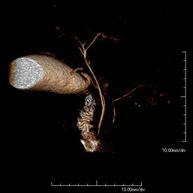

- Angio-RM Aorta abdominal

Prueba diagnóstica no invasiva que consiste en el estudio de la arteria aorta abdominal, obteniendo imágenes de alta definición anatómica mediante el empleo de un campo electromagnético y ondas de radio (con un emisor y un receptor). Es indispensable el uso de contraste paramagnético (Gadolinio). Sin embargo, no utiliza radiación ionizante. La calidad de las imágenes permite realizar reconstrucciones en 2D y 3D. Está indicado en aquellos pacientes con enfermedad vascular (aterosclerosis), estudio de aneurismas, en estudios pre-quirúrgicos de lesiones adyacentes a la aorta abdominal como "mapa" vascular, etc.

- Angio RM Aorta-ilíaca

Prueba diagnóstica no invasiva que consiste en el estudio de la arteria aorta abdominal de las arterias ilíacas, obteniendo imágenes de alta definición anatómica mediante el empleo de un campo electromagnético y ondas de radio (con un emisor y un receptor). Es indispensable el uso de contraste paramagnético (Gadolinio). Sin embargo, no utiliza radiación ionizante. La calidad de las imágenes permite realizar reconstrucciones en 2D y 3D. Esta prueba está especialmente indicada como estudio pre-quirúrgico (mapa vascular) antes de intervenciones percutáneas o quirúrgicas de aorta abdominal y arterias ilíacas, estudio complementario en pacientes con isquemia de miembros inferiores, etc.

Prueba diagnóstica no invasiva que consiste en el estudio de la arteria aorta abdominal, obteniendo imágenes de alta definición anatómica mediante el empleo de un campo electromagnético y ondas de radio (con un emisor y un receptor). Es indispensable el uso de contraste intravenoso paramagnético (gadolinio). Sin embargo, no utiliza radiación ionizante. La calidad de las imágenes permite realizar reconstrucciones en 2D y 3D. Está indicado en aquellos pacientes con enfermedad vascular (aterosclerosis), estudio de aneurismas, en estudios pre-quirúrgicos de lesiones adyacentes a la aorta abdominal como "mapa" vascular…

- Angio-RM Aorta iliaca

Prueba diagnóstica no invasiva que consiste en el estudio de la arteria aorta abdominal, obteniendo imágenes de alta definición anatómica mediante el empleo de un campo electromagnético y ondas de radio (con un emisor y un receptor). Es indispensable el uso de contraste intravenoso paramagnético (gadolinio). Sin embargo, no utiliza radiación ionizante. La calidad de las imágenes permite realizar reconstrucciones en 2D y 3D. Esta prueba está especialmente indicada como estudio pre-quirúrgico (mapa vascular) antes de intervenciones percutáneas o quirúrgicas de aorta abdominal, estudio complementario en pacientes con isquemia de miembros inferiores…